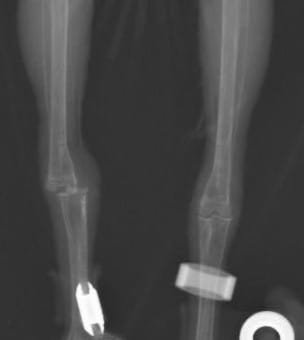

レントゲン検査では右の足根関節が脱臼していることがわかりました。

この場所ははめてもすぐに外れてしまいそうな場所です。ただテーピングをするのもいじったりする可能性もあるため、特に麻酔とかはかけず用手ではめてからそのままアンクレットは付けずケージで安静にしてもらいました。